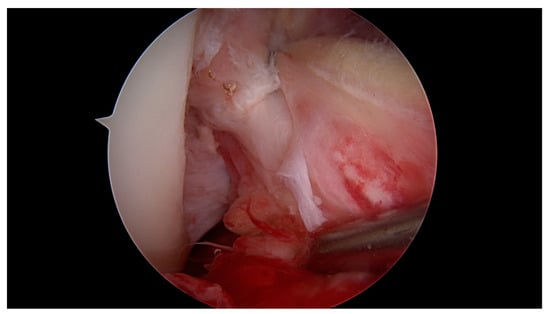

All surgeries were performed under spinal anaesthesia with the affected leg placed in an adjustable leg holder and with administration of an intravenous antibiotic prophylaxis. An examination under anaesthesia of the knee was performed prior to surgery in order to confirm ACL instability. The standard anterolateral and anteromedial portals were established to perform the arthroscopy to confirm all suspected findings with a probe. The ACL was assessed regarding tear pattern and tissue quality. When a proximal tear pattern with good tissue quality was identified (Figure 2), the patient was deemed eligible for arthroscopic ACL repair using SA: a labral scorpion suture passer (Arthrex, Naples, FL, USA) was used to pass a No. 2 FiberWire® (Arthrex, Naples, FL, USA) 3 times approximately 1 cm distal to the tear through the ACL remnant (Figure 3 and Figure 4). The femoral tunnel was drilled in anatomic manner within the footprint with 130 degrees knee flexion using a spade tip drill pin (Arthrex, Naples, FL, USA). An arthroscopic 45 degrees awl was used to perform a microfracture near the femoral footprint to enhance healing (Figure 5). Afterwards, a shuttling loop was passed through the femoral tunnel. The tibial drilling guide (Smith and Nephew, Andover, MA, USA) was placed at the anterior centre of the tibial footprint and a small skin incision at the anteromedial aspect of the proximal tibia was established to allow drilling and shuttling of a loop through the tibial tunnel. The tibial and femoral shuttling loop as well as the FiberWire® suture were retrieved through the anteromedial portal, the latter two placed in the tibial shuttling loop and passed through the tibial tunnel. Using the femoral shuttling loop, the SA construct containing a FiberTape® (Arthrex, Naples, FL, USA) armed TightRope® (Arthrex, Naples, FL, USA) and the FiberWire® were carefully shuttled through tibia and femur so that the TightRope® button flipped at the femoral cortex. The FiberTape® was fixed distally at the anteromedial tibia with a 4.75 SwiveLock® (Arthrex, Naples, FL, USA) with the knee in full extension. Subsequently, the FiberWire® suture and TightRope® tensioning suture were knotted on tension completing the ACL repair (Figure 6). Concomitant meniscal injuries were addressed either with direct repair (RapidLoc®, Mitek Products, Westwood, MA, USA) or with cautious partial resection when repair was deemed not feasible due to the configuration of the tear or pre-existing degenerative meniscopathy (Table 1). Concomitant chondral injuries were carefully smoothed or prudently underwent nano-fracture under direct vision.

Figure 6. Completed arthroscopic ACL repair using suture augmentation (SA).